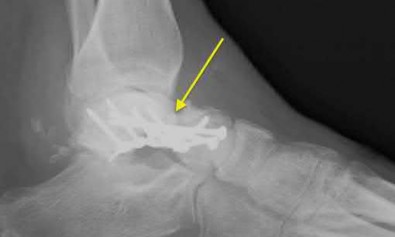

A 25-year-old male sustains an ankle fracture dislocation and undergoes open reduction and internal fixation. He returns to clinic five months following surgery complaining of continued ankle pain and instability with weight bearing. His immediate post-operative AP radiograph is seen in Figure A. Which of the following could have prevented this patient from developing persistent pain?

The patient presents with continued ankle pain and instability following open reduction and internal fixation. The radiograph in figure A demonstrates inadequate restoration of fibular length, likely leading to continued tibiotalar instability.

Illustration A demonstrates fibular malreduction with dislocation of the fibula anterior to the tibial incisura. Illustration B shows a comminuted fibula fracture along with a measurement of length from an intact fibula. The arc from the lateral process of the talus to the peroneal groove of the distal fibula is known as the "dime" sign and should remain unbroken if fibular length has been restored. Illustration C demonstrates the use of a push-pull screw and lamina spreader to regain length intraoperatively for a comminuted fibula fracture.

Chu and Weiner review management of malunions of the distal fibula. The authors state that restoration of fibular length, alignment and rotation leads to reduction of the talus, provides a buttress to talar motion in the setting of an incompetent deltoid, and allows the syndesmotic ligaments to heal at the appropriate tension.